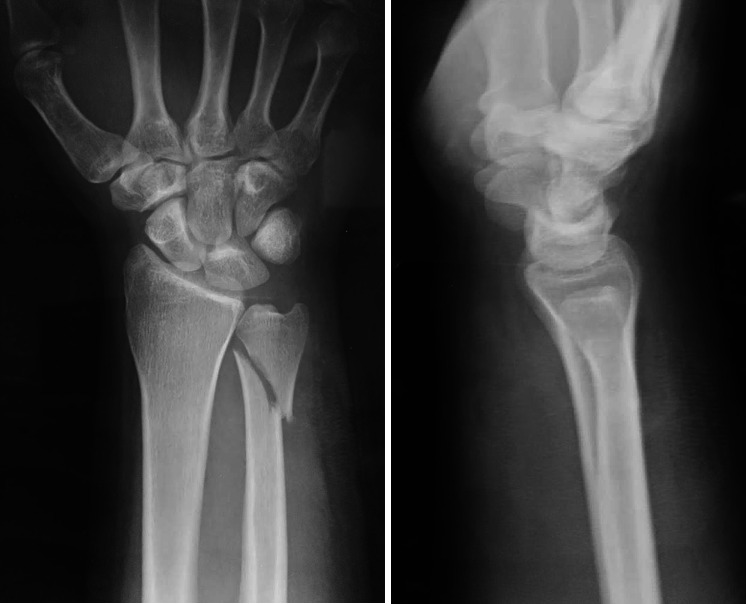

Objective: The purpose of this study is to investigate the outcomes of the use of a 2.7 mm semitubular hook plate for internal fixation of unstable metaphyseal ulnar fractures. Methods: Between January 2015 and July 2019, 30 consecutive patients with a recent unstable distal ulnar fracture were included in this prospective case series. All patients were subjected to follow-up with the time of union, range of motion, pain using a Visual Analog Scale (VAS), and radiological and functional outcome using the quick Disabilities of the Arm, Shoulder, and Hand (DASH) score and Mayo wrist score after 12 months. Results: The mean age of the patients was 45.3 ± 10 years. There were 18 males (60%) and 12 females (40%), and there were 16 patients associated with distal radius fractures (53.33%). According to the AO classification of distal ulnar fractures, 3 fractures were type A2.1 (10%), 9 were type A2.2 (30%), 8 fractures were type A2.3 (26.67%), and 10 fractures were type A3 (33.33%). All fractures have been united with a mean duration of 9 ± 1.4 weeks, the mean supination was 81.4° ± 3.5°, the mean pronation was 81.3° ± 4.5°, the mean flexion was = 71.7° ± 3.6°, and the mean extension was = 81.7° ± 3.4°. The mean VAS was 1.1 ± 1 points, the mean DASH score was 9.3 ± 5.6 points, and the mean Mayo wrist score was 88.5 ± 7.2 points; 17 patients were excellent (56.67%) and 10 patients were good (33.33%) while 3 patients had satisfactory outcome (10%). Conclusion: Using the 2.7 mm semitubular hook plate is a successful choice for internal fixation of unstable distal ulnar fractures isolated or associated with distal radius fractures with a favorable union time, functional outcome, and range of motion with minimal complications.